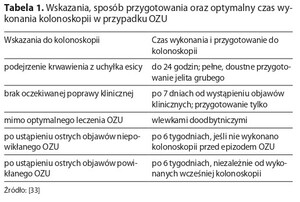

Uchyłki jelita – omówienie aktualnego stanu wiedzy